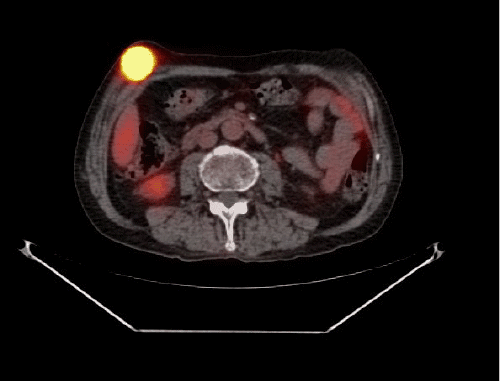

Following a minor procedure, the patient received pathology results. A tumor board discussion at the VAMC determined the need for further staging, leading to a PET/CT scan in which multiple foci of FDG activity were identified in the chest, abdominal wall, and bilateral thighs. To facilitate chemotherapy, a port was placed in September 2019. The patient then underwent palliative FOLFOX chemotherapy, achieving an initial response. Unfortunately, the disease progressed, and the patient passed away in August 2020.

Figure 1. PET/CT Demonstrating FDG-avid Activity in Soft Tissues. Published With Permission

In our case, the skeletal muscle metastases were the first indication that his esophageal adenocarcinoma, which had been treated almost four and a half years earlier, had recurred. His subsequent PET/CT scan demonstrated additional areas of FDG-avidity that were not clinically apparent, underlining the role of these advanced imaging modalities. We elected to remove the symptomatic lesions as a palliative measure.